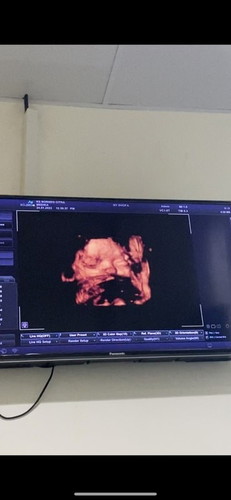

Hai bunda2 alhamdulillah aku hri ini USG trakhir di 36w2d udah 3kg tp setelah di usg usia khamilan malah udah 37/38mgg krna bayi besar. Tafsiran dokter masih 2mgg an lg lahiran, panggul aman lebar bisa lahiran normal semoga di 37w sdh kontraksi bun. Krna kalo sampe 39-40mgg tambah besar lg ddenya takut smpe 4kg n nnti bisa SC atau normal tp robekannya besar🥺 #firstmom #36w2d ##pleasehelp